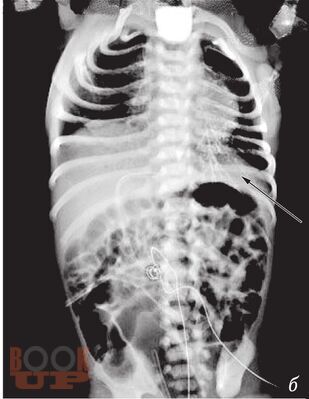

В методическом пособии описаны наиболее распространенные аномалии и пороки развития пищеварительного тракта у детей, а также лучевые методы исследования, с помощью которых диагностируют такие аномалии и пороки.

Пособие иллюстрировано фотографиями оригинальных рентгенограмм и схемами, облегчающими понимание изложенной темы.